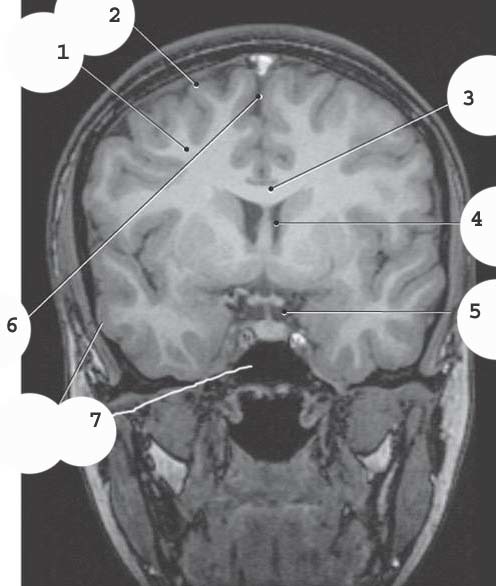

1

Superior Sagittal sinus